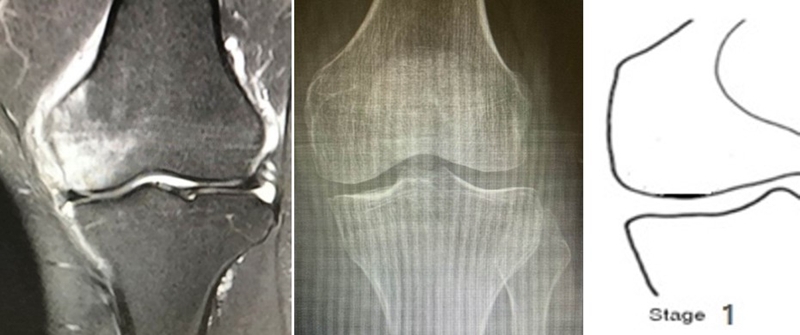

目前SONK诊断最常用的分期方法是1979年Koshino提出的分期法。Koshino分期基于临床和影像学的结果,将SONK分为四个阶段:

Ⅰ期:患者有膝关节症状,但影像学正常;

Ⅱ期:X线显示负重区变平,软骨下信号升高,周围有骨硬化;

Ⅲ期:受影响区域扩大和软骨下塌陷;

Ⅳ期:病变周围骨硬化和髁突周围骨赘形成的退行性阶段。

1979年Koshino分期